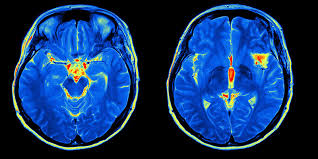

Nei video sulle neuroscienze di 2 minuti si spiegano gli argomenti delle neuroscienze in 2 minuti o meno. In questo video, si discute del neuroimaging, che copre quattro dei più comuni tipi di neuroimaging: tomografia assiale computerizzata (CAT), imaging a risonanza magnetica (MRI), tomografia ad emissione di positroni (PET) e imaging a risonanza magnetica funzionale (fMRI).

LA NUOVA PSICHIATRIA E’ LA NEUROSCIENZA

michele fonti psichiatra e le neuroscienze.jpg